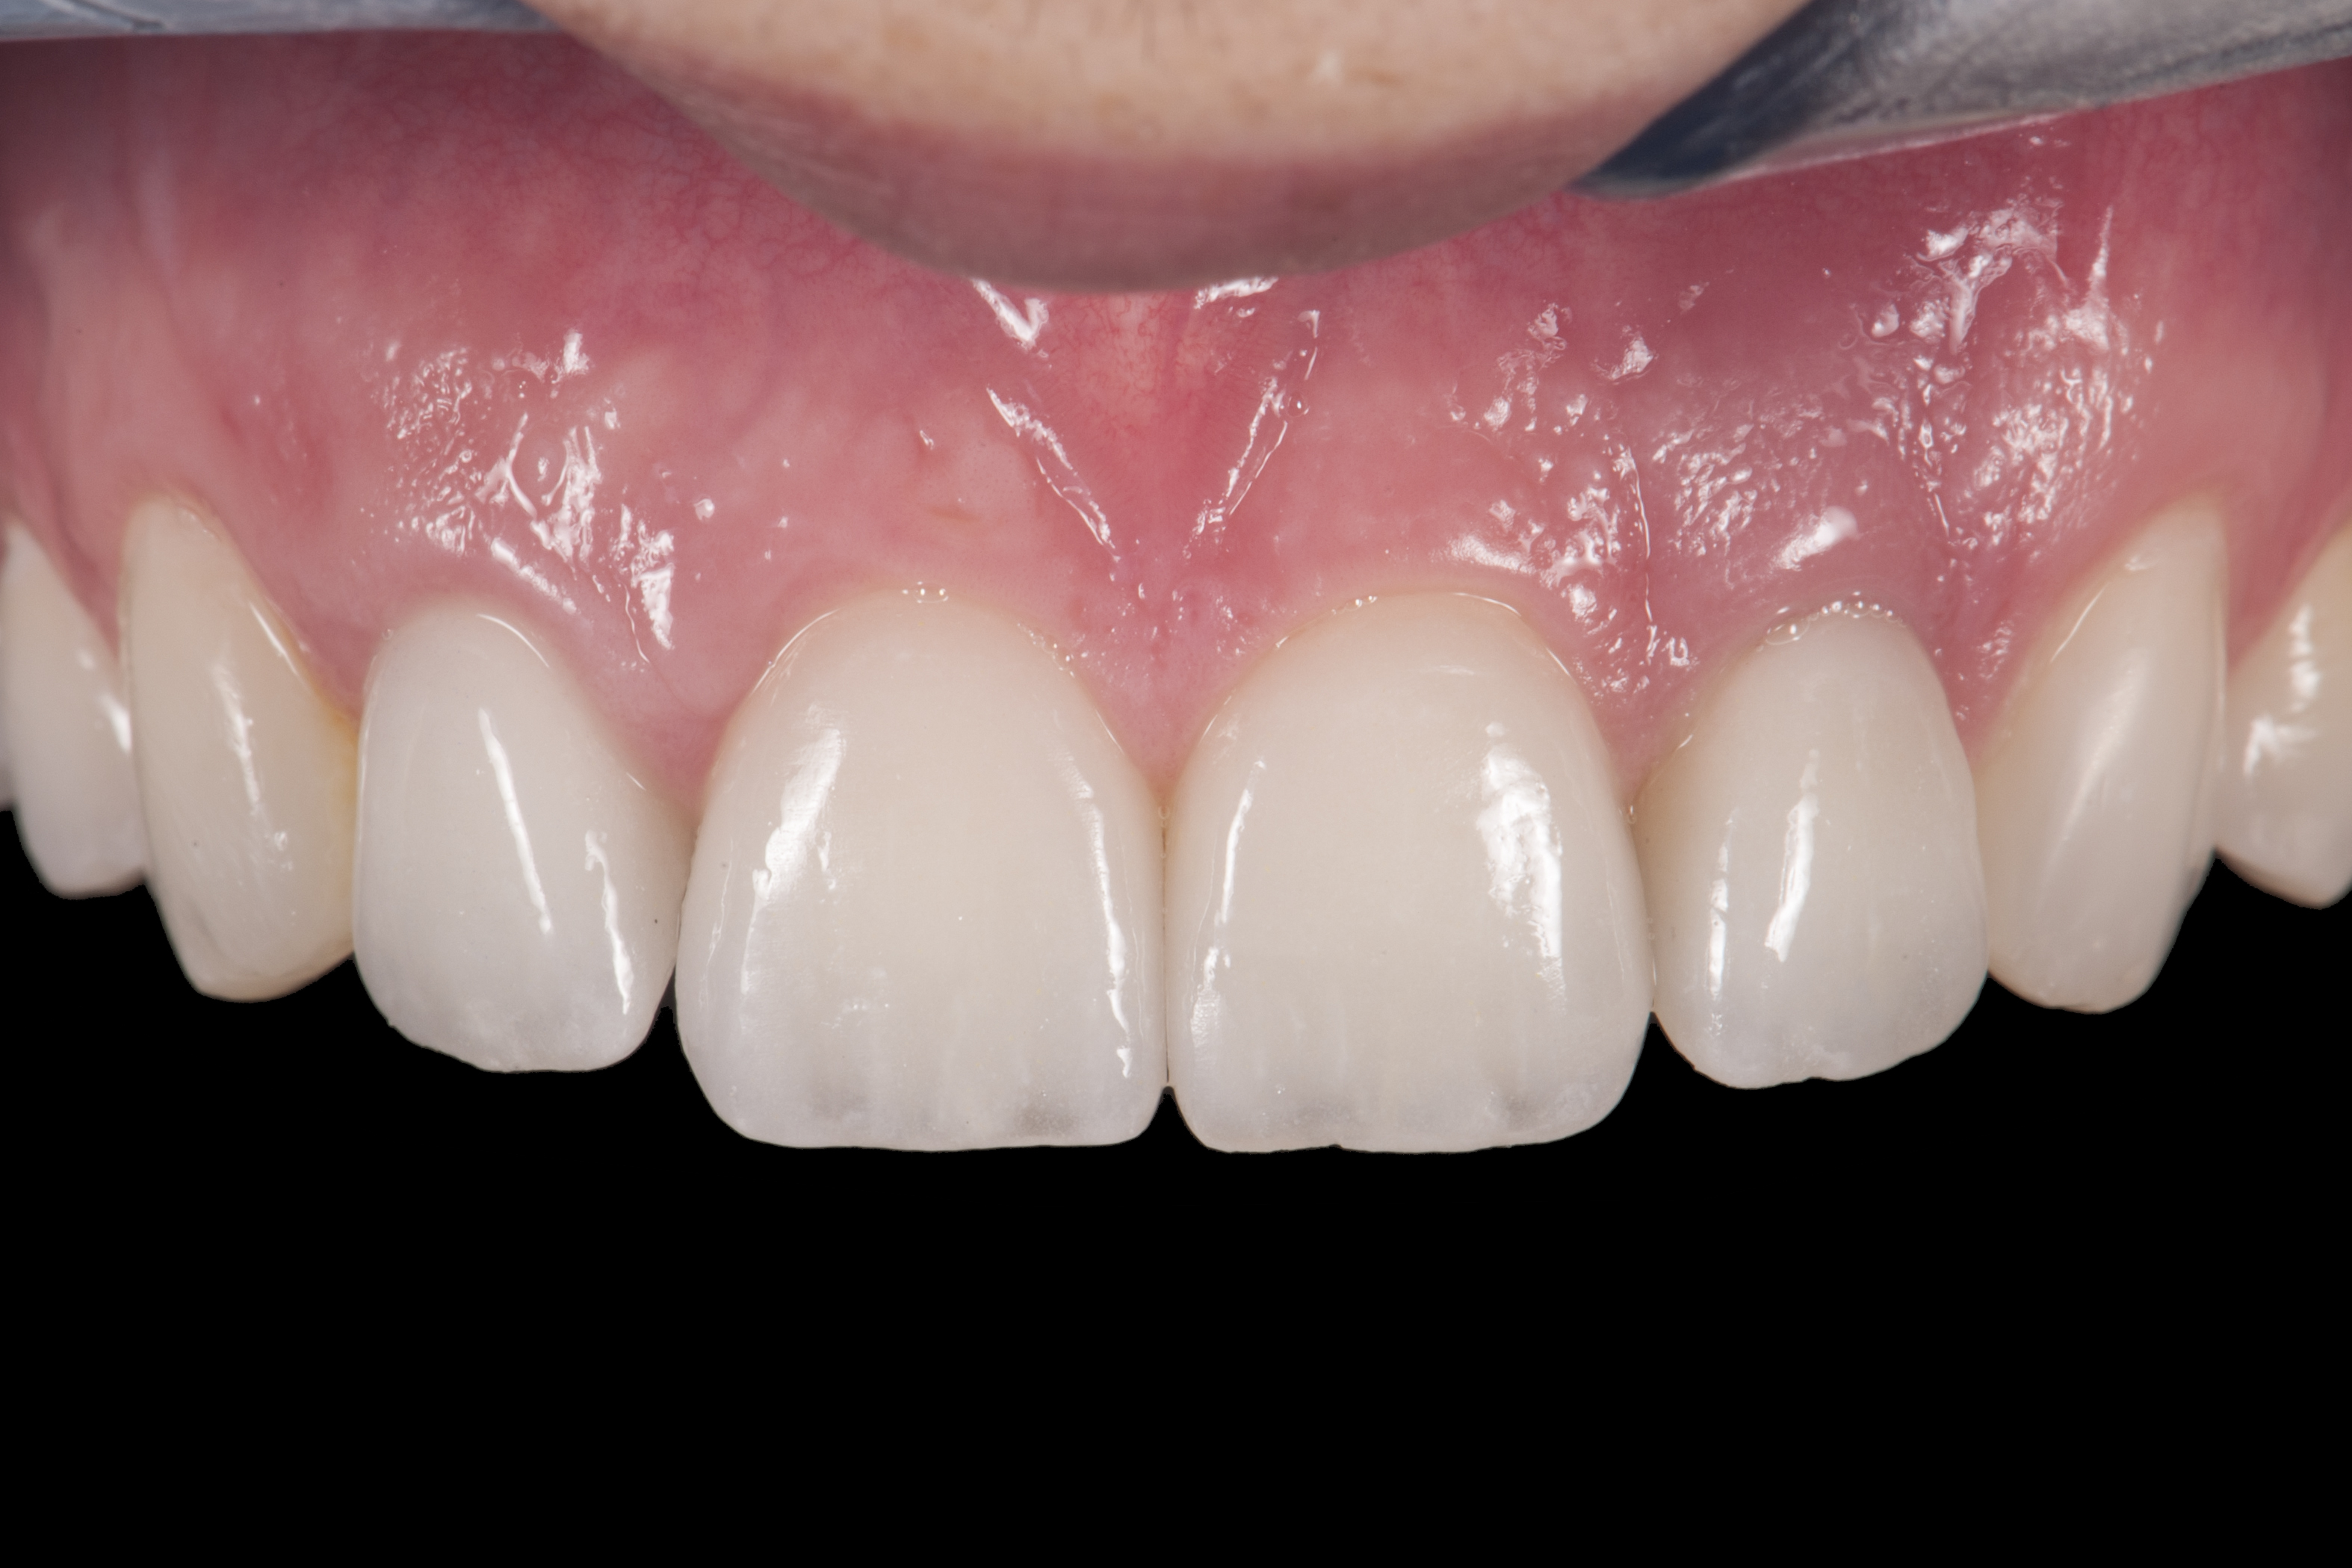

When the patient returned, the fit was evaluated in the mouth. Once verified, the internal surface of the framework was etched with a 9.5% hydrofluoric acid for 90 seconds and then salinized. After etching the enamel surface with phosphoric acid for 30 seconds and applying the primer (Single Bond Plus, 3M ESPE) to both the internal surface of the framework and the enamel, the zirconia bridge was bonded with a dual-cure resin cement (RelyX™ ARC, 3M ESPE). After the procedure, the patient ended up with a long-term, high-strength esthetic restoration advantaged by the bonding potential of fledspathic ceramic (Figure 20 through Figure 24). Six years after placement, the prosthesis had remained in place with no complications.

(20.) Facial view of final single-wing, modified zirconia resin-bonded bridges.

Figure 20

(21.) Smile view.

Figure 21